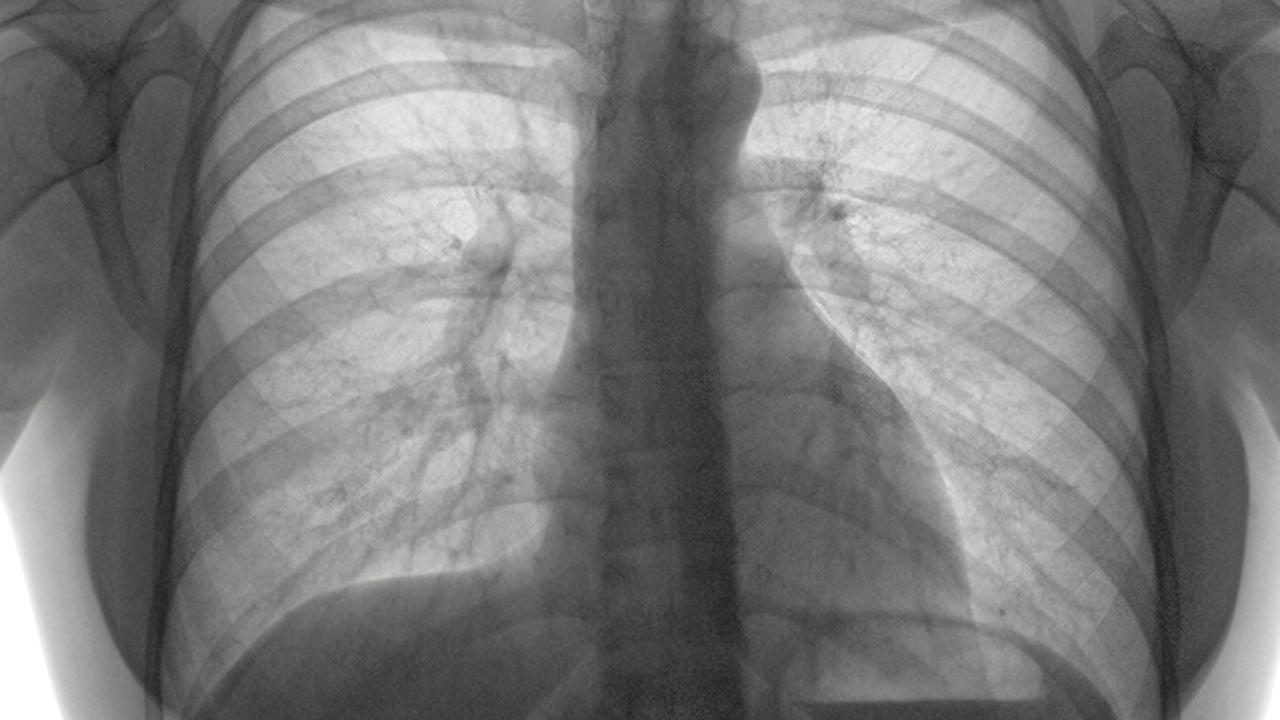

肺癌是一种常见的恶性肿瘤,其发病原因复杂,包括吸烟、环境污染、职业暴露及遗传因素等。早期发现和规范化治疗对提高患者生存率至关重要。济南的这几家医院在肺癌诊疗领域各具特色,能够为患者提供个性化的治疗方案。